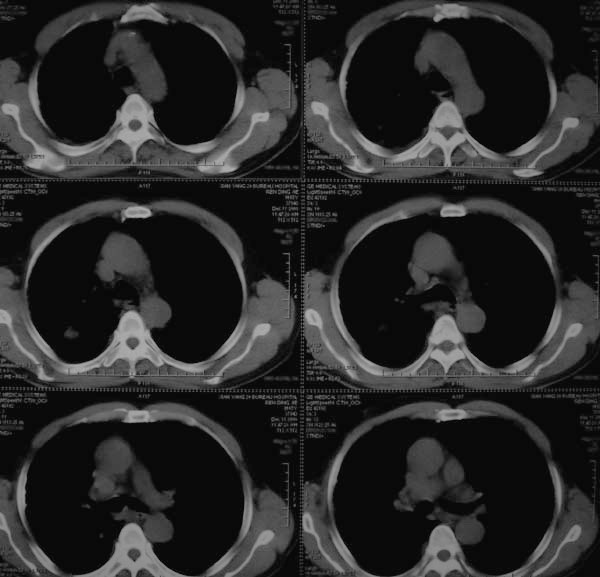

标题: CT17173:M65Y,咳嗽一月。请会诊 [打印本页]

标题: CT17173:M65Y,咳嗽一月。请会诊

考虑结核可能性大

首先考虑右肺继发性肺结核。

右肺多发病灶,右上肺及下肺背段均有灶,考虑结核,